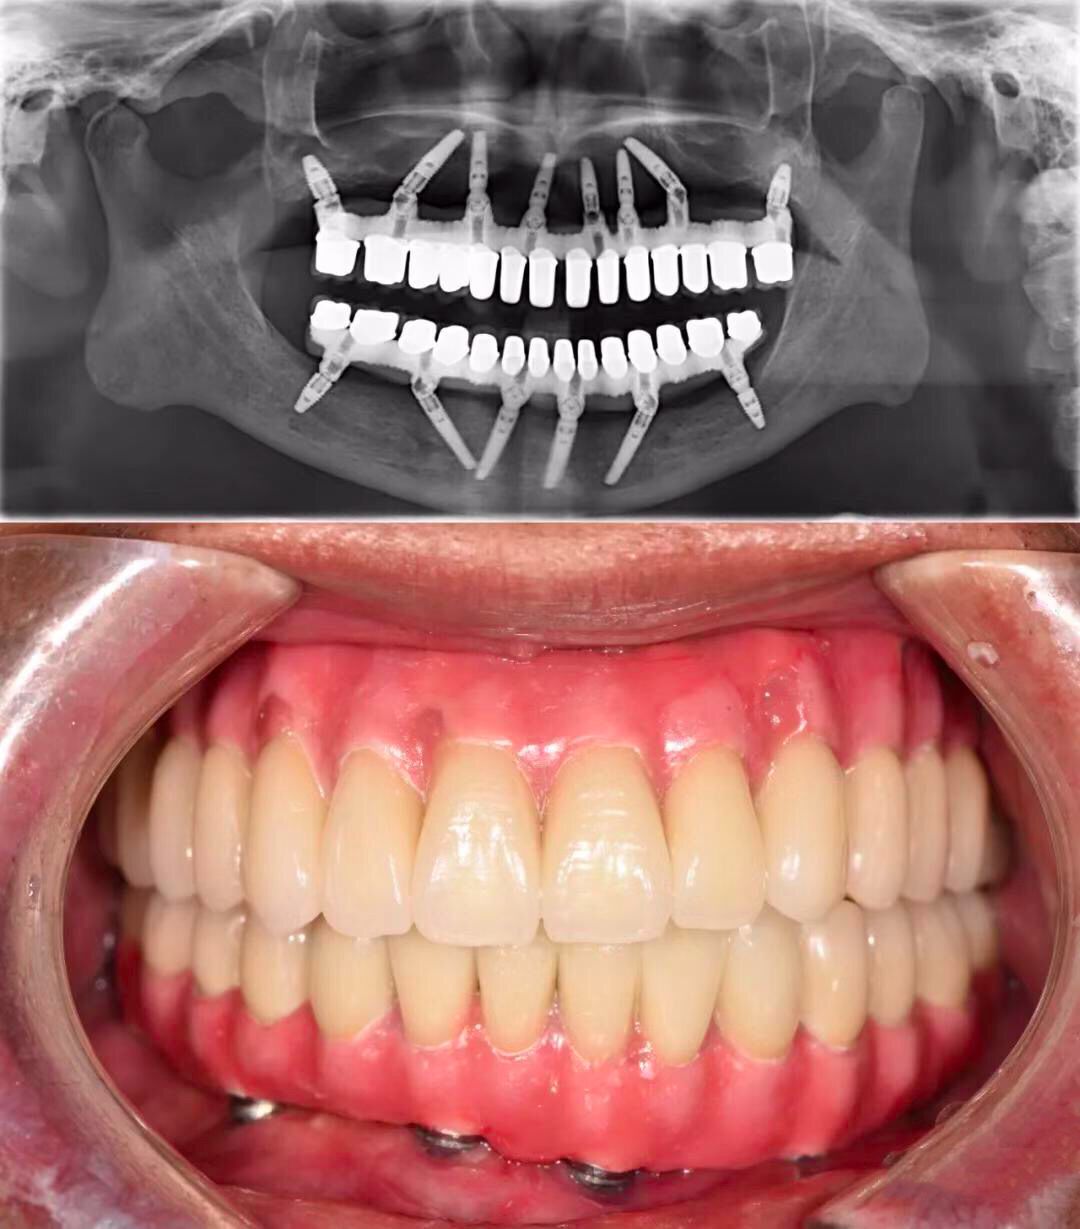

殊不知全*活口**动义齿,不仅功能比天然牙齿相差一大截,咀嚼效力不高,使用也不方便。全口种植义齿也是一种选择,可以较好地恢复咀嚼功能。

但现实是,并不是每个无牙患者,都拥有「口腔里开一辆奔驰」的财力。

全口种植义齿的花费,相当于「口腔里开一台奔驰」(@种牙匠黄建生 供图)